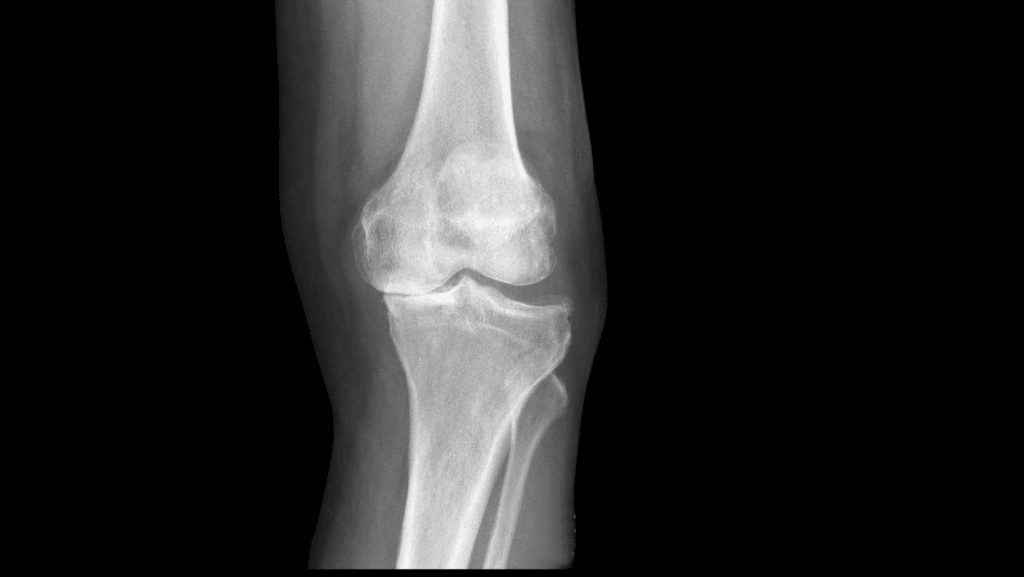

- l’imaging non è particolarmente utile nella diagnosi di sindrome della bandelletta ileotibiale;